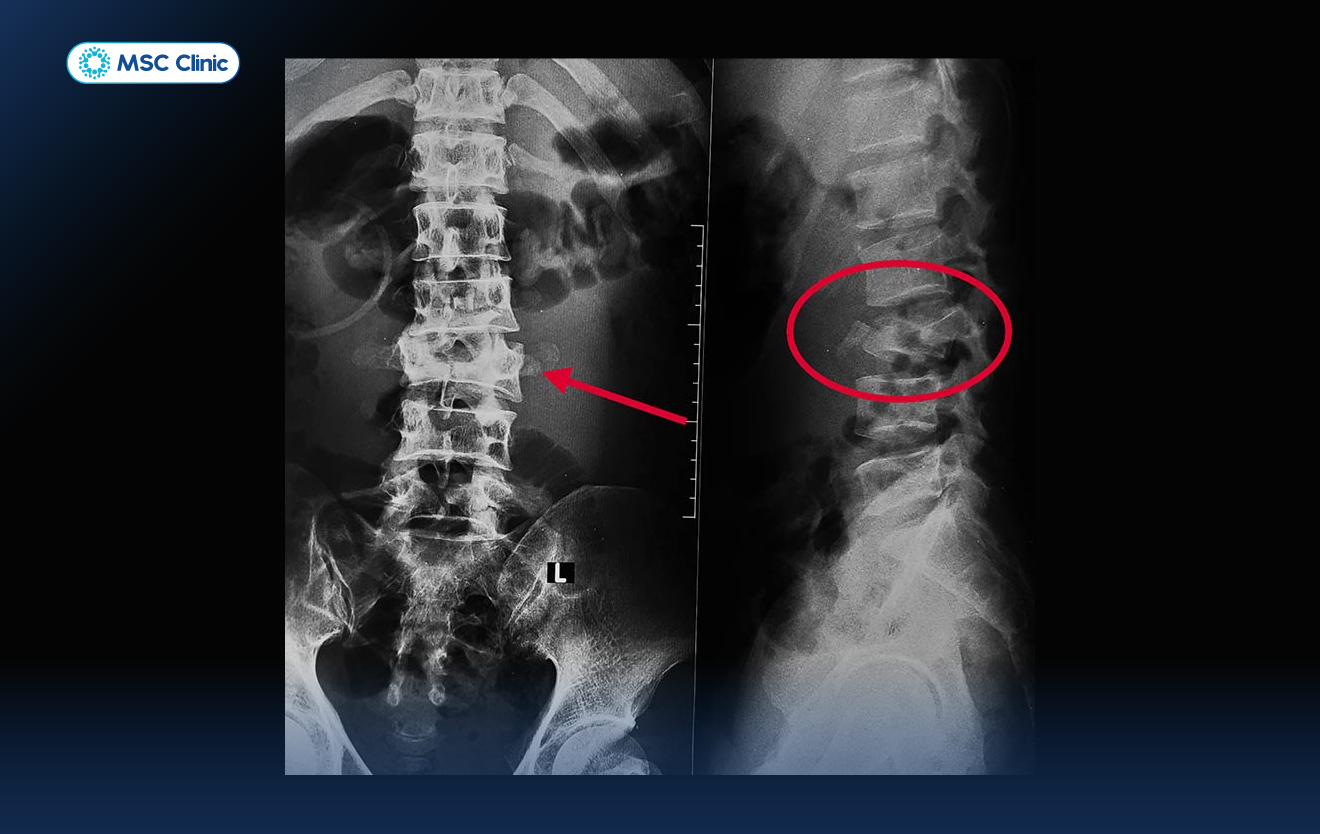

Hình ảnh đốt sống thắt lưng bị nứt vỡ do chấn thương

MSC Clinic sử dụng hệ thống máy X-quang kỹ thuật số thế hệ mới, giúp cho hình ảnh thu được sắc nét, có độ phân giải cao, hỗ trợ bác sĩ phát hiện rõ các bất thường như hẹp khe khớp, gai xương, mất đường cong sinh lý, hay lệch trục đốt sống.